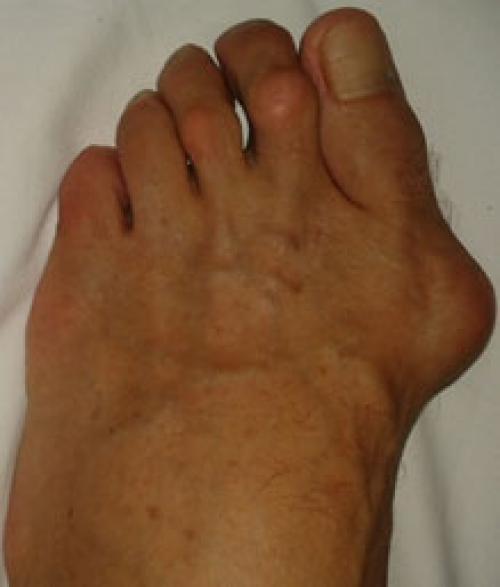

Вальгусное отклонение первого пальца — прогрессирующее дистрофическое заболевание стопы, при котором большой палец отклоняется наружу, а в области его сустава образуется экзостоз или "шишка". Помимо косметического дефекта, деформация приводит к нарушению ходьбы, вызывает боль и часто требует хирургического вмешательства. Пациенты с патологией не могут носить обычную обувь, а на тяжёлых стадиях — и ортопедическую. Это приводит к снижению подвижности и нарушению психологического равновесия больного.

Вальгусное отклонение большого пальца составляет более 70 % от всех ортопедических патологий. Заболеванием в 95 % случаев страдают женщины. Нарушение возникает после 30-40 лет и вызвано гормональными изменениями : яичники вырабатывают меньше половых гормонов — эстрогенов, оказывающих защитное воздействие на соединительную ткань. Соединительная ткань непрерывно обновляется, подвергается перестройке в ответ на нагрузку и повреждение. Структурным компонентом соединительной ткани являются коллагеновые волокна. Основная функция коллагена заключается в том, чтобы придавать соединительной ткани прочность и долговечность. Дефицит эстрогенов ведет к снижению образования коллагена в соединительной ткани. В результате капсульно-связочная система, состоящая из соединительной ткани, теряет прочность.

Другая причина заболевания — наследственная предрасположенность . В большинстве случаев, если нарушение есть у матери, его выявляют и у дочери.

Основным фактором, способствующим развитию деформации стопы, является ношение неудобной обуви — узкой и на каблуке более трёх-четырёх сантиметров. Усугубить патологию может беременность, продольное плоскостопие, травмы стопы и голени.